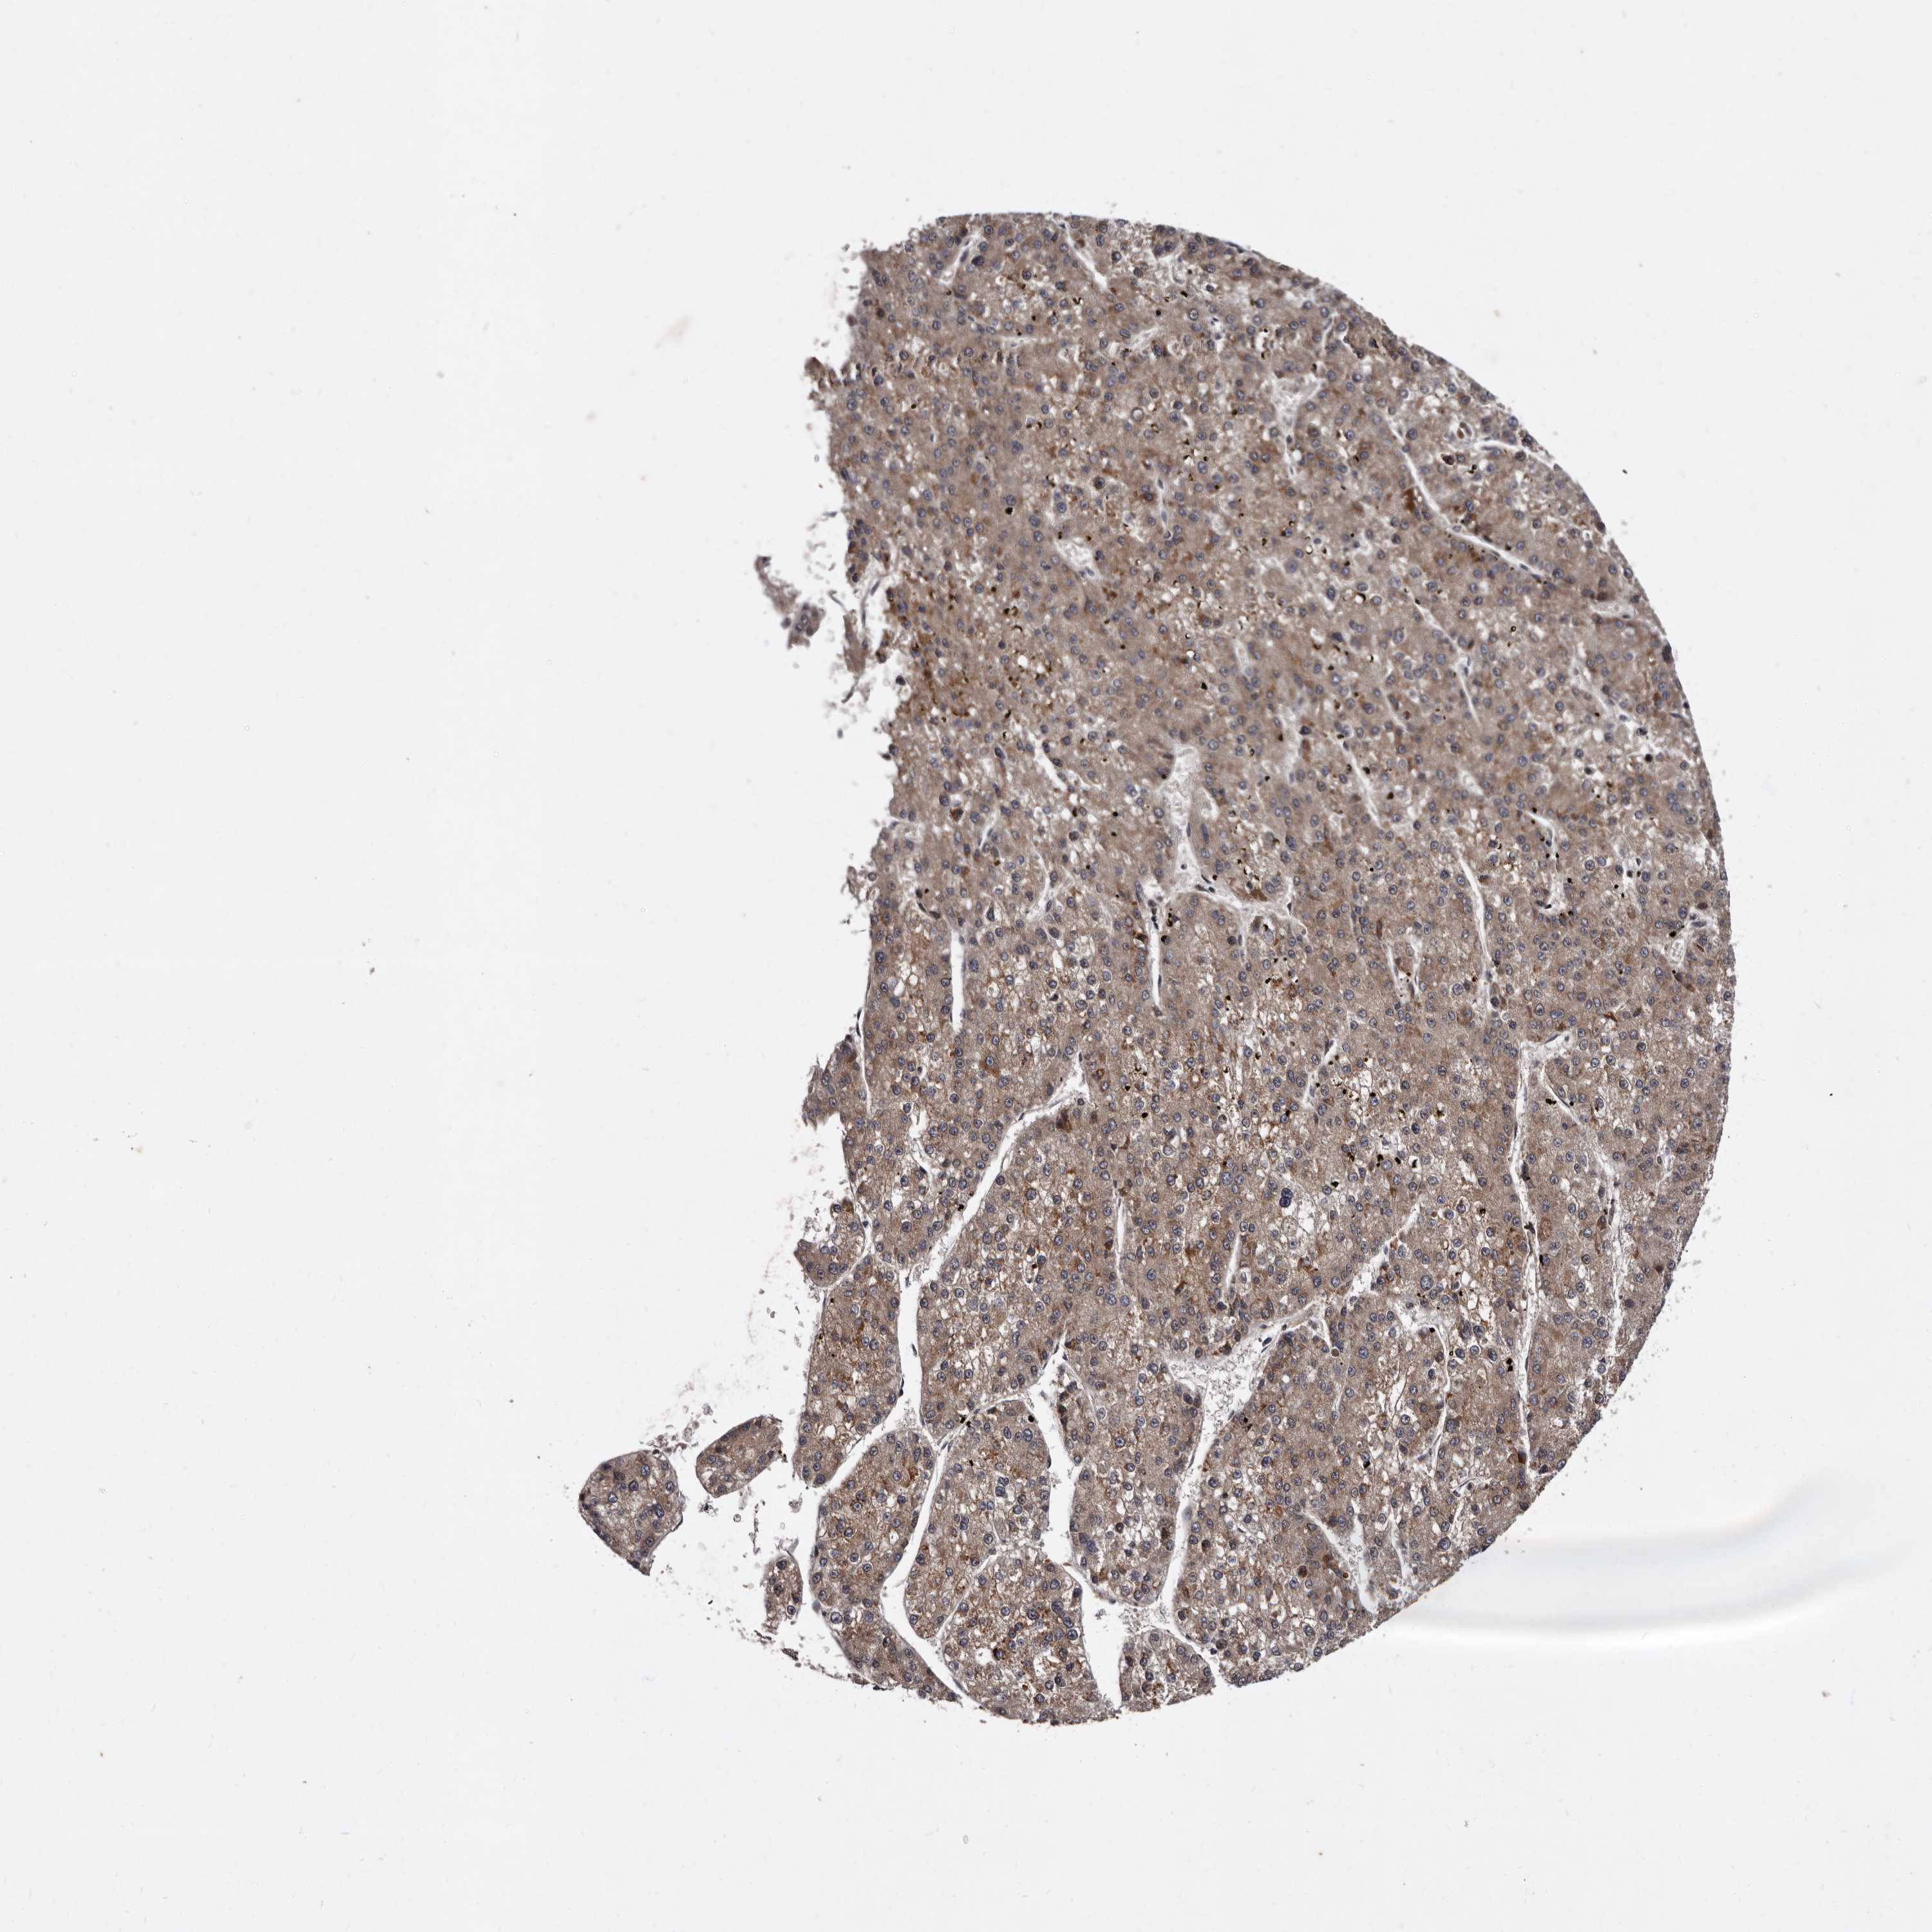

LIVER CANCER - Protein expressioni

A mouse-over function shows sample information and annotation data. Click on an image to view it in a full screen mode. Samples can be filtered based on level of antibody staining by selecting one or several of the following categories: high, medium, low and not detected. The assay and annotation is described here.

Note that samples used for immunohistochemistry by the Human Protein Atlas do not correspond to samples in the TCGA dataset.

Antibody stainingi

Antibody staining in the annotated cell types in the current human tissue is reported as not detected, low, medium, or high, based on conventional immunohistochemistry profiling in selected tissues. This score is based on the combination of the staining intensity and fraction of stained cells.

Each image is clickable and will lead to virtual microscopy that enables deeper exploration of all samples and also displays staining intensity scores, fraction scores and subcellular localization as well as patient and tissue information for each sample.

Antibody HPA025690

Staining

High

Medium

Low

Not detected

Intensity

Strong

Moderate

Weak

Negative

Quantity

>75%

75%-25%

<25%

None

Location

Nuclear

Cytoplasmic/membranous

Cytoplasmic/membranous,nuclear

Cholangiocarcinoma

Carcinoma, Hepatocellular, NOS